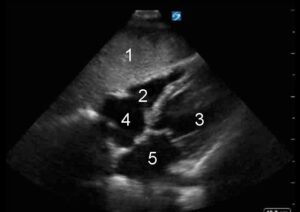

Apicale 4 camere (A4C)

Piano di scansione che interseca l’apice cardiaco e le valvole atrio-ventricolari, mostrando entrambi i ventricoli e gli atri.

Posizione della sonda

La finestra si trova generalmente a livello del quarto o quinto spazio intercostale tra la linea emiclaveare sinistra e la linea ascellare anteriore sinistra, tuttavia, vi è ampia variabilità anatomica individuale sia in senso medio-laterale che cranio-caudale. L’indicatore della sonda è diretto verso il cavo ascellare sinistro del paziente. Il fascio ultrasonoro viene quindi diretto cranialmente verso la testa del paziente e la sonda viene ruotata fino a posizionare il marker orientativamente alle ore 3.

- Ventricolo destro

- Ventricolo sinistro

- Atrio destro

- Atrio sinistro

L’apice del ventricolo sinistro dovrebbe essere al vertice dello schermo, con il setto interventricolare disposto verticalmente al centro dello schermo. Si osservano sulla destra dello schermo le sezioni sinistre del cuore e viceversa. Il ventricolo sinistro è attraversato dal piano di visione nelle sue porzioni inferosettale e anterolaterale. Alla giunzione atrioventricolare si osservano medialmente il lembo anteriore della valvola mitrale e lateralmente il lembo posteriore. È visibile anche il ventricolo destro con la valvola tricuspide, solitamente più vicina all’apice cardiaco rispetto alla valvola mitrale. Gli atri sono visibili nella parte bassa dell’immagine.

Da questa immagine è possibile valutare:

- Ventricolo sinistro: questa finestra è una delle migliori per la valutazione del ventricolo sinistro. Un ventricolo normofunzionante ha un ispessimento simmetrico della parete in sistole, con chiusura pronta della valvola mitrale e un suo rapido avvicinamento all’apice cardiaco e pronta apertura valvola aortica sistolica. Un infarto della arteria coronarica discendente anteriore è ben apprezzabile in questa visione, comportando discinesie del segmento apicale del ventricolo.

- Valvola mitrale: i lembi di una mitrale normale dovrebbero rimanere sotto all’anulus mitralico con adeguata chiusura in sistole. Un prolasso o ribaltamento significativo o una netta mancata chiusura della valvola dovrebbero allarmare in merito a una possibile insufficienza mitralica. Si possono osservare anche calcificazioni o alterazioni reumatiche della valvola.

- Atri: normalmente sono simili in dimensioni tra di loro, e ridotti rispetto ai ventricoli.

- Valvola tricuspide: ben visibile da questa finestra, normalmente si apre interamente in diastole e rimane confinata all’anulus con buona chiusura in sistole. Il prolasso dei lembi valvolari o una chiusura incompleta possono indicare insufficienza mitralica.

Ventricolo destro: questa è la visione ottimale per la valutazione della funzionalità del ventricolo destro, che normalmente dovrebbe apparire più piccolo del sinistro e convergere leggermente sotto all’apice cardiaco. Se all’apice cardiaco i ventricoli appaiono simmetrici e

- le dimensioni del ventricolo destro sono uguali o superiori a quelle del sinistro è lecito sospettare una dilatazione ventricolare destra. Segni di buona contrazione del ventricolo destro sono dati dall’ispessimento della parete libera e dal rapido avvicinamento della valvola tricuspide all’apice cardiaco. Inoltre è possibile calcolare un TAPSE (Tricuspid Annular Plane Systolic Excursion), un parametro affidabile della funzione sistolica del ventricolo destro. Il TAPSE si ottiene tramite l’utilizzo dell’ M-mode orientato sull’anulus tricuspidalico. I suoi valori normali nell’adulto sono generalmente superiori ai 15-16 mm.